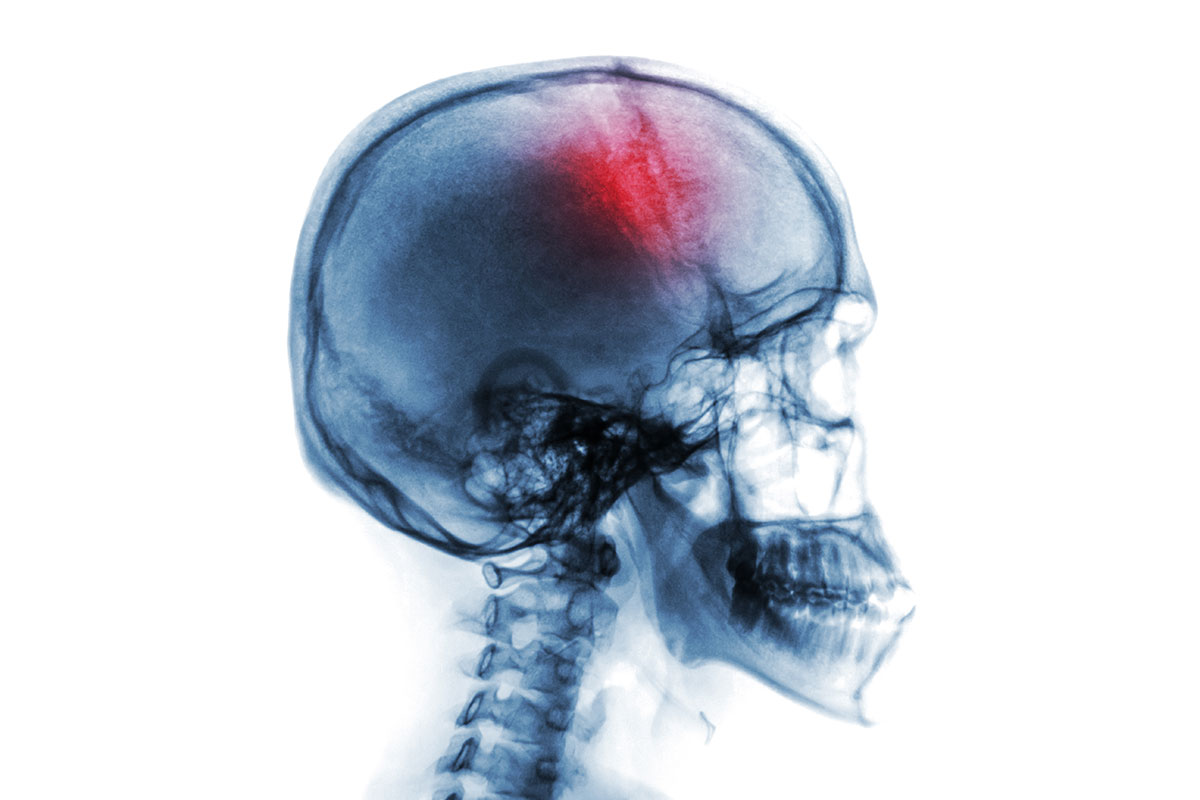

Los vasos sanguíneos que llevan la sangre del corazón al cerebro se llaman arterias. El cerebro requiere de un suministro constante de sangre, ya que contiene el oxígeno y las sustancias nutritivas que necesita para funcionar. Un accidente cerebrovascular (ACV), también denominado evento vascular cerebral (EVC), ocurre cuando una de estas arterias del cerebro se obstruye o se rompe. Como resultado, la parte del cerebro que no recibe sangre empieza a morir.1 El cerebro controla todo lo que hacemos. Si debido a un accidente cerebrovascular un área localizada del cerebro no recibe el oxígeno necesario, la parte del cuerpo controlada por esa área podría verse afectada. Por eso, los accidentes cerebrovasculares pueden causar problemas con el movimiento, la visión, el habla, etc. 2 un accidente cerebrovascular ocurre cuando una de las arterias del cerebro se obstruye o se rompe y la parte del cerebro que no recibe sangre empieza a morir Los dos tipos de accidentes cerebrovasculares. Hay dos tipos de accidente cerebrovascular: isquémico y hemorrágico. 2 Accidente cerebrovascular isquémico. Ocurre cuando una arteria en el cerebro es obstruida. 1 Accidente cerebrovascular hemorrágico. Ocurre cuando un vaso sanguíneo en el cerebro se rompe y derrama sangre dentro o alrededor del cerebro. Una elevada presión sanguínea y la presencia de aneurismas pueden llevar a que la pared de la arteria se debilite y se rompa. 1 Un aneurisma es el debilitamiento de una arteria, lo que lleva a que esta se dilate como una burbuja de paredes finas. A medida que crece, la pared se vuelve cada vez más débil y puede romperse. Si se rompe, la sangre se derrama del cerebro, o alrededor de él. 1